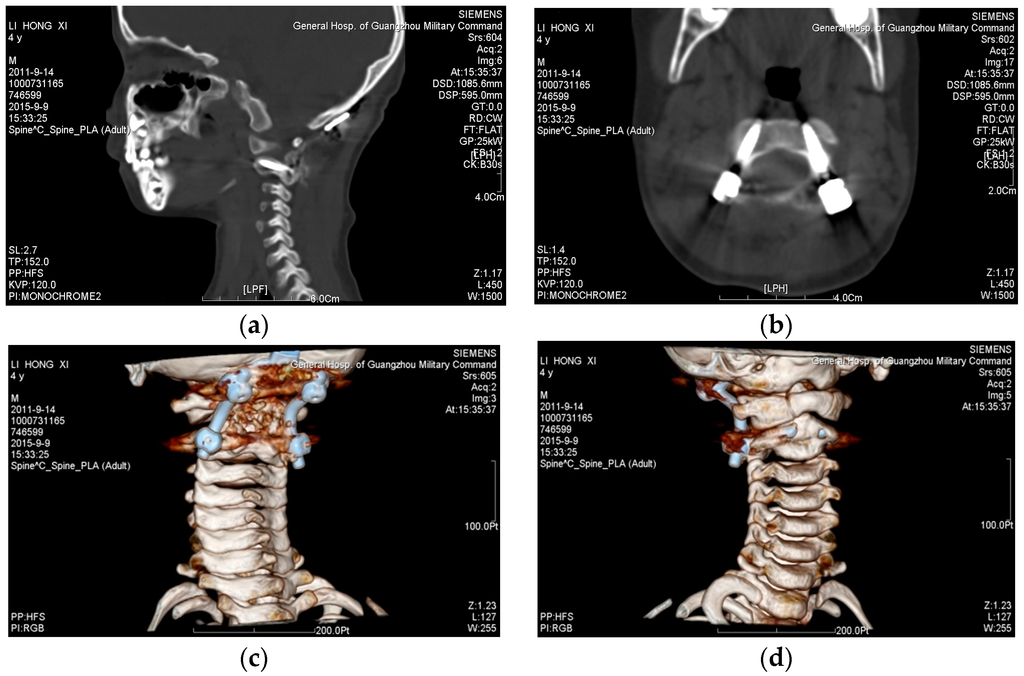

- The Biograph 64 PET/CT apparatus (SIEMENS, Munich, Germany) was used to obtain scan data, with a scan condition of 120 kv,150 mAs; scan slice thickness of 0.5 mm; and a scanning time of 10–15 s. The factor that affects the geometrical accuracy is the scan slice thickness, which would impact the surface fitting accuracy. The data from a thin-layer CT scan of the cervical vertebrae of the patient was imported into Mimics 16.0 (Materialise, Leuven, Belgium) to extract the target spine. Store this as STL (binary) to be imported into Geomagic software (3D syestems, Rock Hill, SC, USA). Elimination of the noise points inside the bone to obtain the 3D entity was accomplished by executing the following process: extract surface—construct patches—construct grids—surface fitting, and store it in the STEP AP203 format; import the data from Geomagic software into SolidWorks software; and integrate the separate 3D entity models into an assembled model to obtain the target spine model (as shown in Figure 1a).